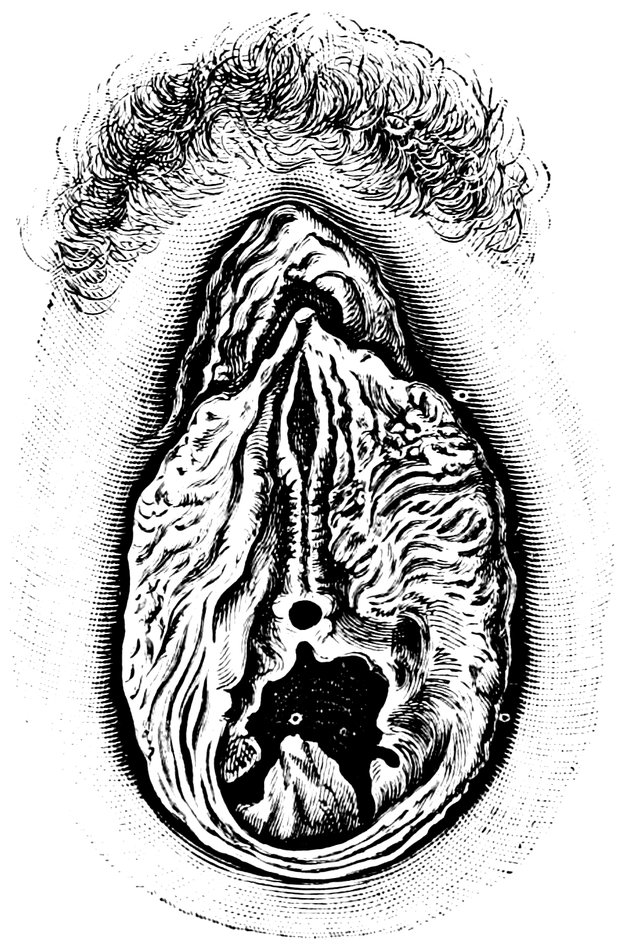

| 12. | Female external genital organs of a virgin | 54 |

| 13. | The external genital organs of a virgin | 55 |

| 15. | Primitive follicles | 58 |

| 16. | Ripening follicles | 61 |

| 17. | Graafian follicles | 62 |

| 18. | Annular Hymen | 64 |

| 19. | Annular Hymen | 64 |

| 20. | Semilunar Hymen | 65 |

| 21. | Annular Hymen with Congenital Symmetrical Indentations | 65 |

| 22. | Fimbriate Hymen | 65 |

| 23. | Deflorated Fimbriate Hymen | 65 |

| 24. | Septate Annular Hymen | 67 |

| 25. | Septate Semilunar Hymen | 67 |

| 26. | Extremely tough Annular Hymen with an obliquely disposed Septum | 67 |

| 27. | Septate Hymen with Apertures of unequal Size | 67 |

| 28. | Septate Hymen with Apertures of unequal Size | 68 |

| 29. | Hymen with rudimentary Septum | 68 |

| 30. | Hymen with posterior rudimentary Septum | 68 |

| 31. | Labiate Hymen with posterior rudimentary Septum | 68 |

| 32. | Hymen with anterior rudimentary Septum | 69 |

| 33. | Hymen with anterior rudimentary Septum projecting in a opiniform Manner | 69 |

| 34. | Hymen with anterior and posterior rudimentary Septa | 69 |

| 35. | Hymen with filiform Process projecting from the anterior Margin | 69 |

| 36. | Hymen in which there are two symmetrically disposed thinned Areas. The left of these is perforated | 69 |

| 37. | Very unusual form of Hymen | 70 |

| 38. | Semilunar Hymen with cicatrized Lacerations in its Border | 70 |

| 39. | Deflorated Semilunar Hymen with laterally disposed symmetrical Lacerations | 70 |

| 40. | Deflorated Annular Hymen with several cicatrized Lacerations | 70 |

| 41. | A. Septate Hymen in which defloration has been effected through one of the Apertures. U. Urethra. Cl. Clitoris. H. Cicatrized Margin. C. Septum. B. Lateral view of Septum | 70 |

| 42. | Deflorated Septate Hymen | 71 |

| x43. | Hymen with larger anterior and smaller posterior Apertures | 71 |

| 44. | Carunculæ Myrtiformes in a Primipara | 71 |

| 45. | Vaginal Inlet of a Multipara, without Carunculæ Myrtiformes. Slight Prolapse of Anterior and Posterior Vaginal Walls | 71 |